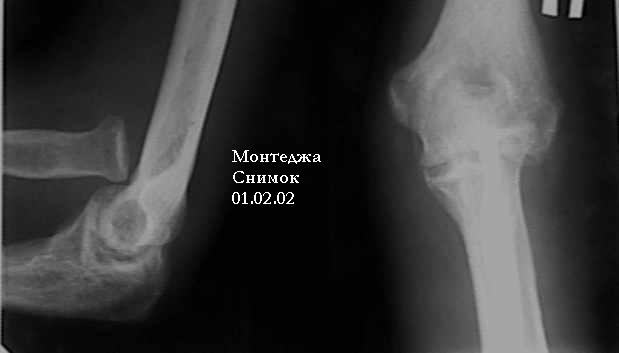

У больного травма в октябре 2001. Перелом Монтеджа разгибательный.Проведена операция металлостеосинтез пластиной, винтами локтевой кости. Вывих головки лучевой кости не диагностирован. В конце февраля 2002 г снята гипсовая повязка. Имеется ограничение сгибания до 115 градусов. Больной обратился в наше лечебное учреждение 07.02.02. Мы предложили ему оперативное лечение. Планируем провести резекцию головки лучевой кости. Есть мнение попытаться вправить головку лучевой кости, провести пластику кольцевидной связки, фиксисировать головку лучевой кости трансартикулярно спицей. Но боюсь, что в момент остеосинтеза была укорочена локтевая кость, поэтому необходимо будет провести резкцию в области диафиза лучевой кости, а затем провести остеосинтез лучевой кости. Рентгенограммы: